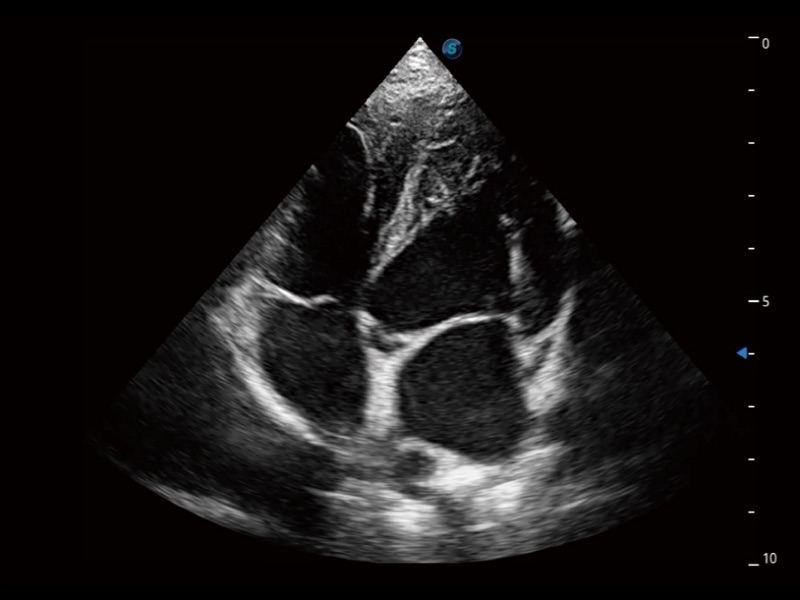

ProPet 70 进一步提升了微米成像算法,更加注重对基础原始图像的还原和保留,在有效减少斑点噪声、增强组织边界显示的同时,避免过度优化丟失真实的解剖信息。

ProPet 70专为动物医生设计,对不同的动物体型和生理结构作出了针对性的优化。通过动物影像专用软件,可满足个性化的应用需求,帮助动物医生获得更精确的诊断数据。

为精细结构及组织边缘提供高清晰度的图像和更大的成像视野。帮助减轻医生的用眼疲劳,快速精准获得测量的数据。